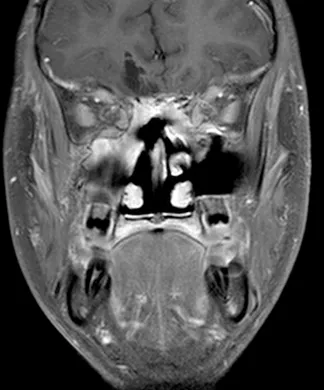

一名15岁、既往健康的男性,因额部头痛加剧、恶心、呕吐和疲劳两周病史就诊。家属注意到在就诊前一个月出现言语失控和非典型行为。他的神经系统检查显示双侧视乳头水肿,无其他局灶性缺损。所有血液检查均正常,血清生殖细胞肿瘤标志物也为阴性。脑和鼻旁窦的计算机断层扫描(CT)和磁共振成像(MRI)扫描显示,右侧有一个5.5 x 4.4 x 5.6厘米的肿块,起源于鼻腔、筛窦和蝶窦。它已侵蚀筛板进入前颅窝。该肿块在CT扫描上未钙化(图1),与脑组织等密度,伴有不均匀的对比增强。该肿块在T1和T2加权MR图像上(图2、3、4)与脑组织等信号,并在钆增强后显示不均匀强化。注意到周围有血管源性脑水肿和占位效应。脊柱MRI未见转移证据。

图2:冠状位T1加权钆增强MRI扫描,证实了起源于鼻腔并延伸至前颅窝的大肿瘤团块的发现。对额叶下部的占位效应和轻微的中线移位是明显的。

图4:冠状位T2加权MRI扫描,证实了颅内肿瘤成分的不均匀实性和囊性性质。病灶周围水肿以及肿瘤相关的中线移位也清晰可见。